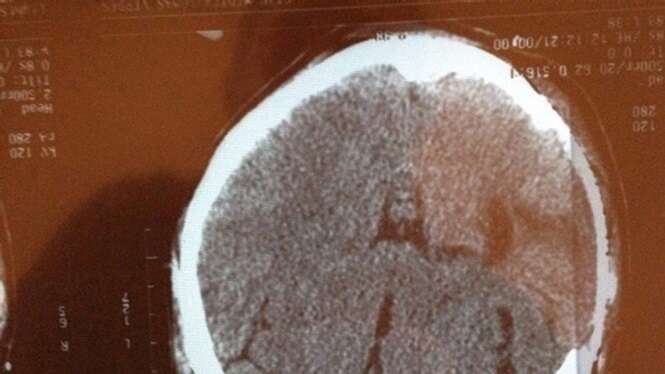

As imagens que você verá a seguir mostram exames de raio-X que são um tanto quanto incomuns.

Os exames mostram objetos pra lá de inusitados inseridos dentro dos corpos de pacientes de várias partes do mundo.

Todos eles certamente farão você estremecer de dor.

Os pacientes certamente tentaram usar tais itens para se dar prazer íntimo, mas acabaram se dando muito mal.